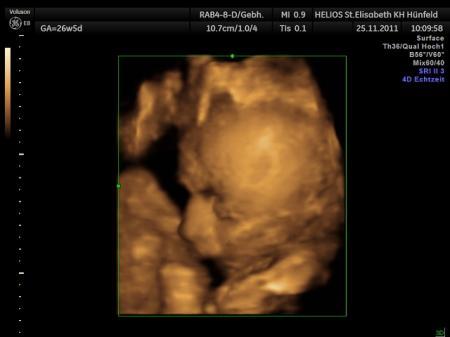

guten abend ihr lieben :-) kommen grad vom arzt, hat mal wieder etwas länger gedauert! unser schatz ist jetzt 40 cm u wiegt 1800 g :-) und liegt jetzt in startposition :-) das freut mich sehr, hab von der drehung gar nix mitgekriegt :-P das letzte mal lag es noch mit dem kopf oben ! 3D foto hat nicht geklappt, hat sich nicht zeigen wollen... ist wohl genauso kamerascheu wie der papa :-) ab morgen bin ich dann 33. woche, also 9. monat.... einfach irre !!!! liebste grüße

Bild zu